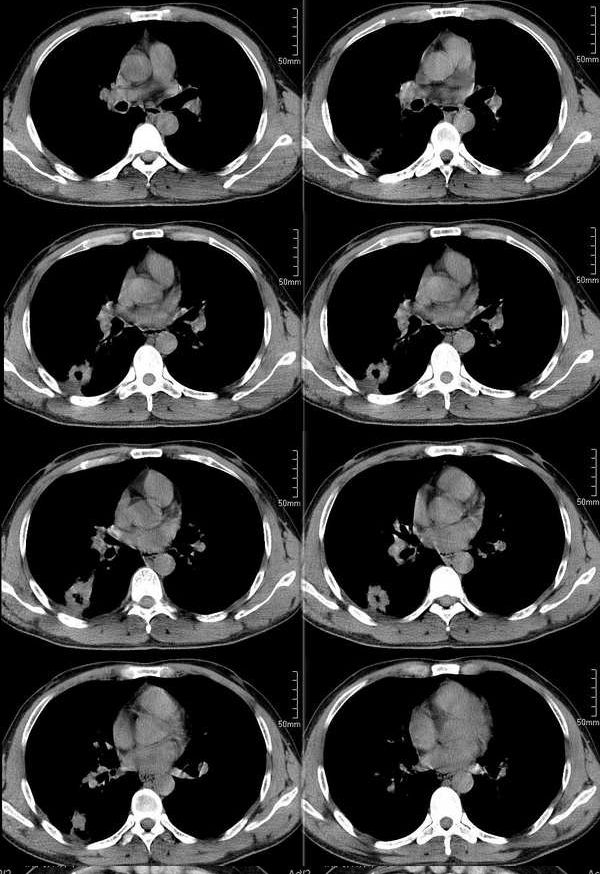

ct2533:张巍 提供 患男,24岁,胸痛数月.

穿刺活检为干酪坏死物.胸壁结核瘤!

ct1240:song7715

病人24岁,身体偏瘦,半月前曾有高烧,现无阳性体征,血项不高。透视时无意发现。

右肺结节病理结果:结核球http://www.radida.com/radinet/read.php?tid=3611

ct1585:liuwensi 提供

m,64y,体检发现右肺上叶后段孤立性结节,纵隔内未见肿大淋巴结影右肺病理是结核球